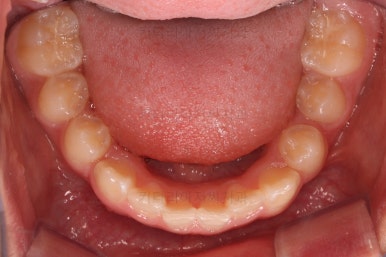

초진 시 입안의 모습입니다.

앞니가 안으로 굽어 들어간 양상인데요. 흔히 "옥니"라고 표현합니다.(뻐드렁니의 반대개념)

전반적으로 치열이 삐뚤삐뚤하고요.

그리고 전반적으로 아래 치열이 윗니에 비해 뒤로 밀려 있어서, 어금니의 맞물림이 좋지 못하고 듬성듬성해 보이는 상황이었어요.